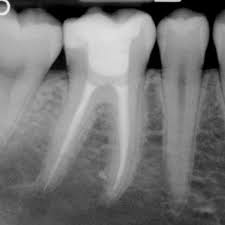

I trattamenti di odontoiatria per adulti e bambini proposti a Fiano Romano e Passo Corese dallo Studio Dentistico Dominici includono la conservativa, ovvero una branca della disciplina dentistica che punta appunto a conservare i denti, anche in caso di carie, fratture e altre problematiche. Secondo l’organizzazione mondiale della Sanità la carie è la malattia cronica più diffusa al mondo, spesso è sottovalutata o non trattata in modo adeguato, comportando forti ricadute sia sulla salute che … sul portafogli. Spesso il paziente non si accorge di avere una carie, che causa dolore solo quando è arrivata in profondità, per questo è importante la regolarità nei controlli periodici presso lo studio dentistico , per poterne diagnosticare celermente l’eventuale presenza con gli appositi strumenti. Grazie alla tecnologia di ultima generazione siamo in grado di diagnosticare le carie invisibili ad occhio nudo o quelle presenti in zone non visibili ( tra un dente e l’altro), utilizzando un sensore laser totalmente indolore che garantisce una diagnosi precisa al 100%. Una volta individuata, la carie verrà eliminata e il dente ricostruito utilizzando speciali resine composite, atossiche e altamente estetiche.